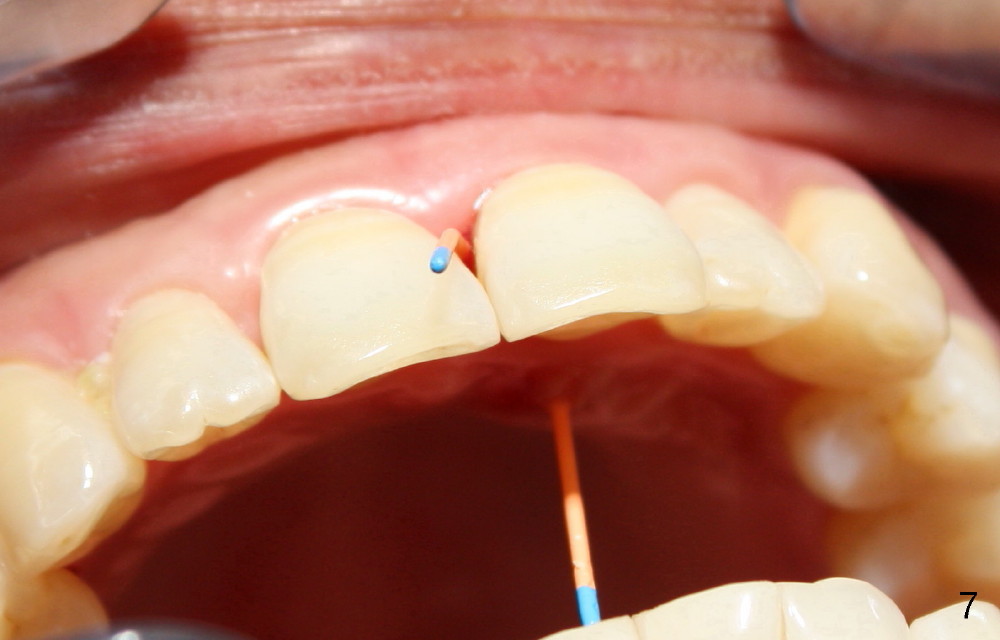

A 60-year-old lady had an abscess mesial to #9 six years ago (Fig.1,2 <), treated as a perio lesion by laser (Fig.3) and osseous surgery without bone graft (Fig.6, followed by CT exam revealing semi-circumferential bone loss (Fig.4,5). When the perio treatment failed, attention was paid to endo aspect (Fig.7-9). In fact the pulp was found to be vital when access to root canal therapy was made. As expected, the treatment failed again. The palatal fistula persisted. The infection was suspected to be a source of remote immediate implant site (#30). The tooth #9 was extracted. It appears that there is a semilunar crack line in the linguomesial root (Fig.12). When the socket healed 2 weeks post extraction (Fig.10), the #30 buccal defect was debrided with bone graft. There was no bone resorption 4 weeks post extraction (Fig.11); a 4.5x17 mm implant was placed (Fig.13-15). An immediate provisional was fabricated (Fig.16-18). Fig.19,20 were taken 3 months post implantation and 7 months post cementation, respectively. Dense bone forms around the implant coronally 4 years 5 months post cementation (Fig.21), while the gingiva is healthy palatally (Fig.22) and buccally (Fig.23).